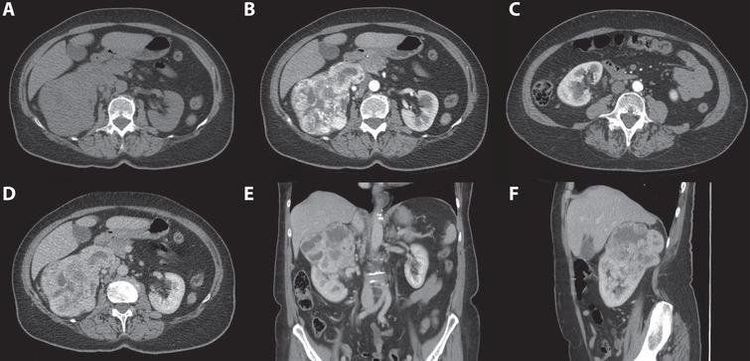

- Chụp các lớp cắt thì động mạch (thì vỏ thận)

Mục đích của thì chụp này là để đánh giá mức độ giàu mạch của tổn thương u, đánh giá tình trạng thuốc thoát ra ngoài lòng mạch nếu có chảy máu do chấn thương thận. Đồng thời thể hiện tình trạng tĩnh mạch dẫn lưu sớm đối với các tình trạng thông động mạch hoặc tĩnh mạch,...Đánh giá khả năng bài tiết của vỏ thận.

- Chụp lớp cắt thì tĩnh mạch (thì nhu mô)

Mục đích của bước chụp này là đánh giá các tổn thương ở u thải thuốc nhanh hay chậm. Đánh giá tình trạng ngấm thuốc của 2 bên tĩnh mạch thận và tĩnh mạch chủ dưới đối với bệnh u thận, từ đó nhìn ra các tổn thương dạng như bị dập hoặc vết vỡ nhu mô ở các chấn thương. Đánh giá khả năng thải thuốc của tủy thận.

- Các lớp cắt thì muộn (thì bài xuất)

Đánh giá hình thái đài bể thận,niệu quản, bàng quang và các bất thường liên quan. Tùy thuộc vào bệnh lý đường dẫn niệu và khả năng bài xuất của thận, có thể xác định thời điểm chụp muộn hơn.